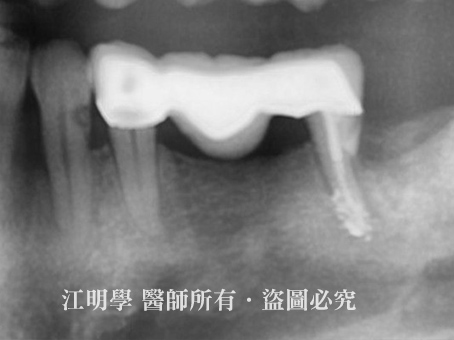

治療後X光